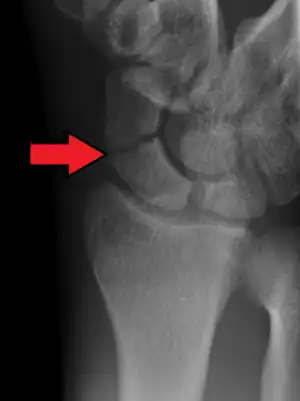

| An X-ray showing a fracture through the waist of the scaphoid | |